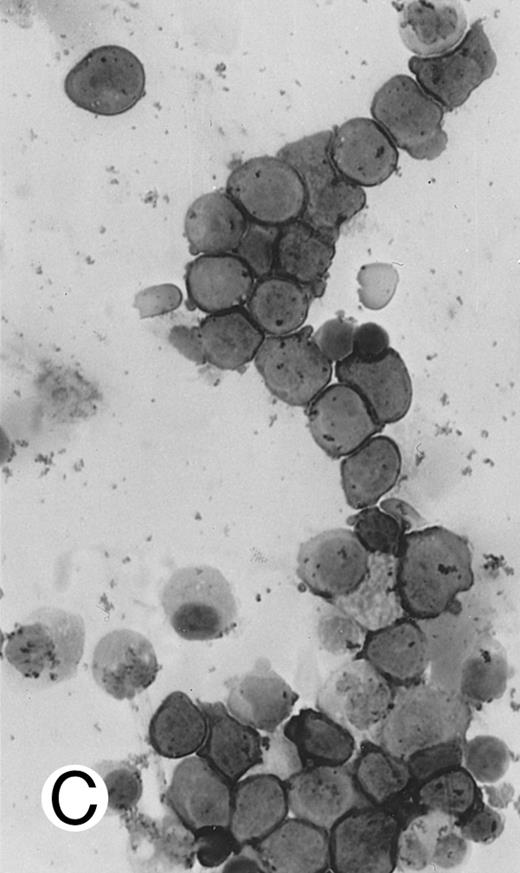

Blastoid NK cell lymphoma (case no. 40). (A) Biopsy shows a diffuse lymphomatous infiltrate with a prominent single-file pattern. (B) The neoplastic cells are medium-sized and possess fine chromatin. Mitotic figures are seen. There is remarkable resemblance to myeloid leukemic infiltration.

Blastoid NK cell lymphoma (n = 2).One patient presented with systemic disease, whereas 1 had localized disease at presentation. Histologically, the infiltrate was diffuse, with a prominent single-file pattern reminiscent of leukemia (Fig 8A). The neoplastic cells were medium-sized and had irregularly folded delicate nuclear membranes, fine chromatin, and tiny nucleoli (Fig 8B). Mitotic figures were easily identified.

In case no. 40, the immunophenotype was CD2− CD3/Leu4− CD4− CD5− CD7+ CD8− CD13− CD33+ CD56+, as analyzed on fresh tissue, and CD3ε+ (weak) CD43+ CD56+ CD68− TdT− and myeloperoxidase-negative on paraffin sections. In case no. 41, the immunophenotype as assessed on paraffin section was CD3ε+ CD43+ CD56+ TdT− and myeloperoxidase-negative. Both cases were EBERs-negative.